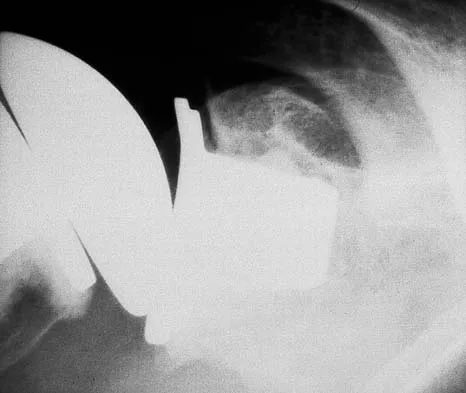

A 37-year-old electrician is diagnosed with a frozen shoulder after sustaining an electrical injury at work 2 weeks ago. Examination reveals that he cannot actively or passively externally rotate or abduct the arm. The glenohumeral joint and scapula move in a 1:1 ratio. Radiographs are shown in Figures 15a and 15b. The best course of action should be

Explanation